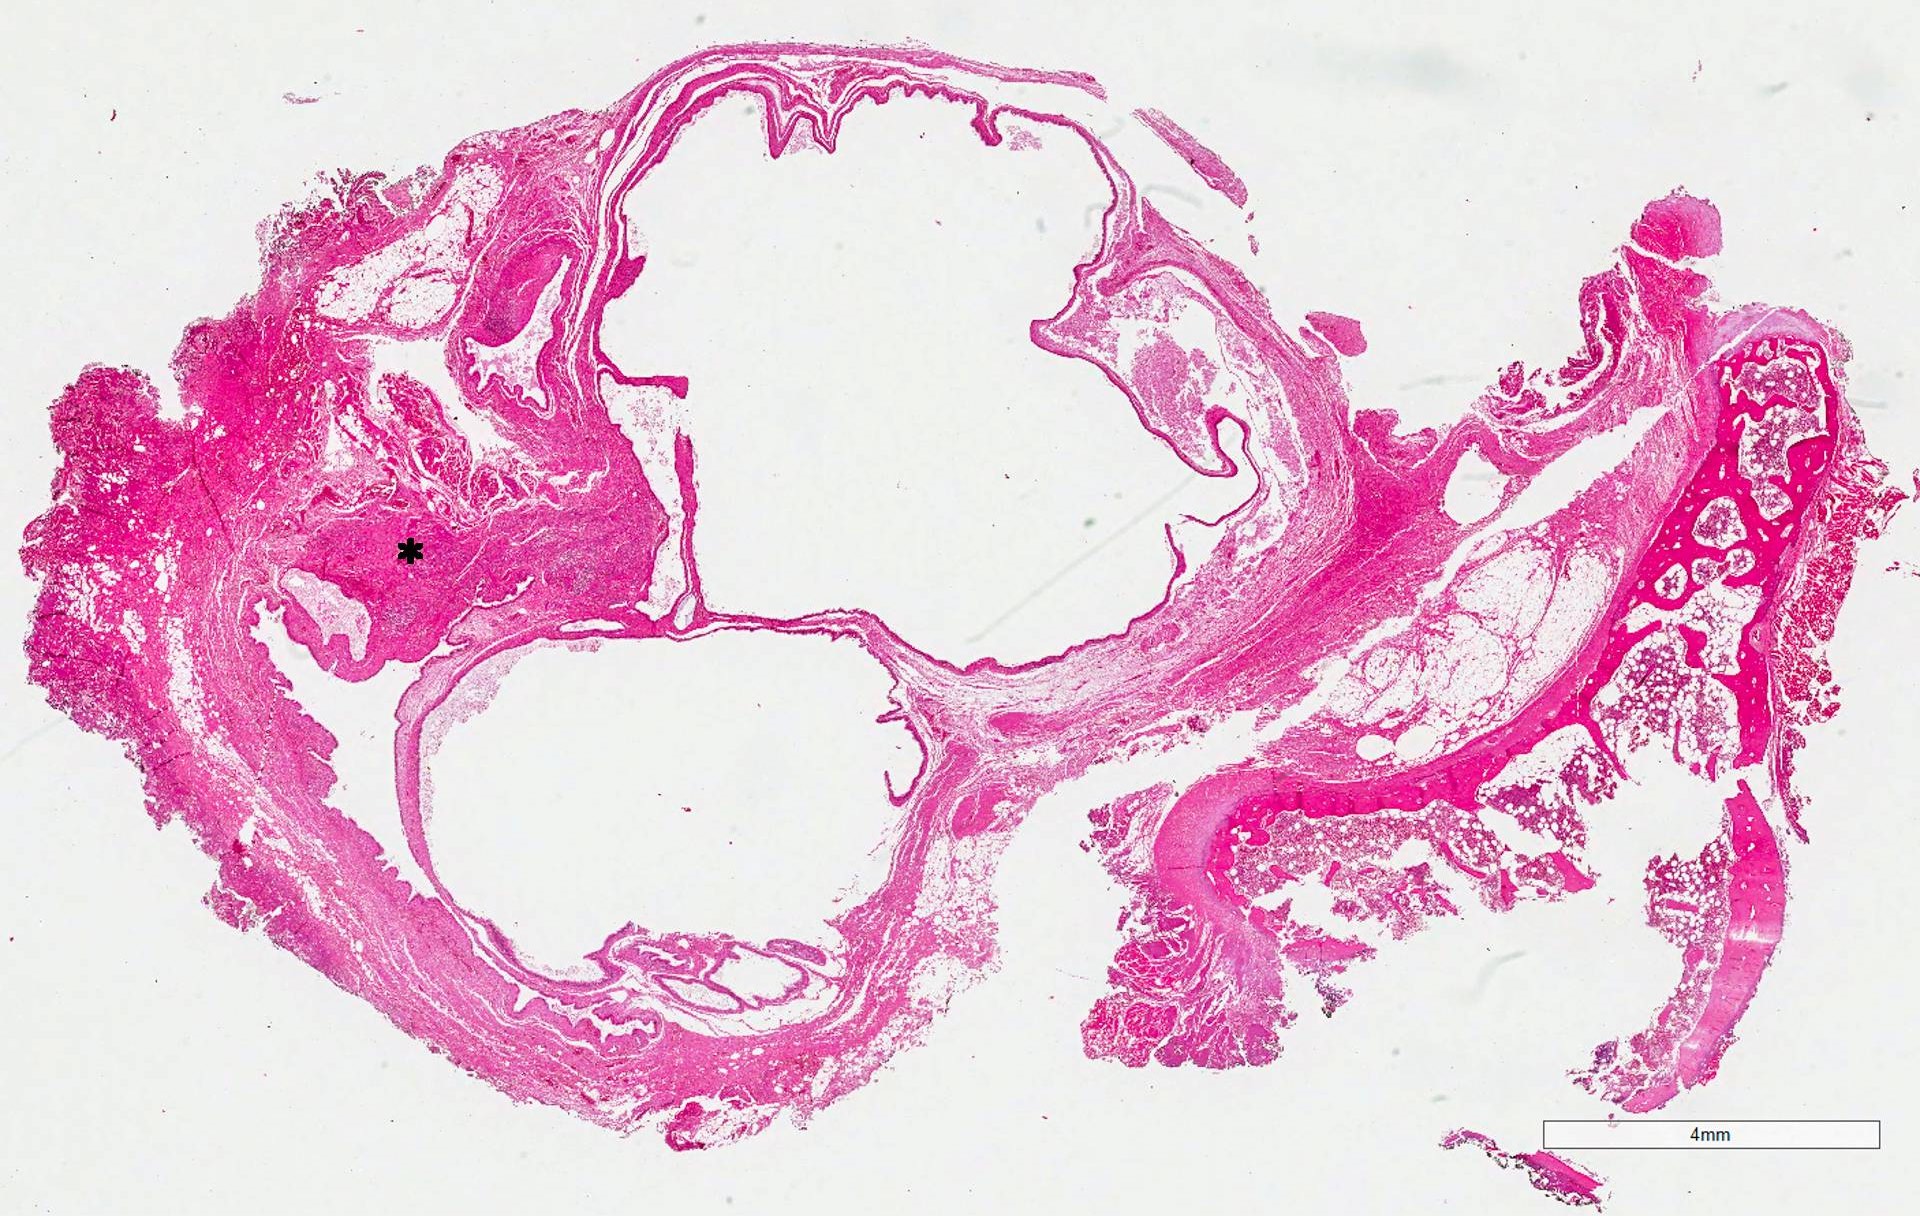

Microscopic (histologic) description

- Type of epithelial lining varies by site, and combinations of the types below can be seen in a single cyst (Head Neck Pathol 2013;7:50):

- Ciliated pseudostratified columnar (respiratory) epithelium in lower neck, perhaps due to its close proximity to upper respiratory tract

- Nonkeratinizing squamous epithelium in higher neck (near tongue and foramen cecum), also can be of metaplastic origin in inflammatory settings

- Stratified cuboidal epithelium at level of hyoid bone

- Very often the cyst is denuded of epithelium, at least focally, which reflects epithelial damage by inflammation

- Secondary inflammation is common, especially in sinus tract (J Pediatr Surg 1984;19:506):

- Intense lymphocytic infiltration, rarely arranged into lymphoid follicles

- Admixture of neutrophils (if the cyst is infected)

- Granulation tissue and fibrosis

- Thyroid follicles in the cyst / duct wall:

- Found in 30% - 60%, with higher yield on serial sections

- More common in infra- versus suprahyoid remnants, on the right paramedian side (Ann Otol Rhinol Laryngol 2000;109:1135)

- Seen in small irregular groups

- Thyroid epithelium may be normal or rarely hyperplastic or neoplastic

- Thyroid tissue often hidden by inflammation (Laryngoscope 2001;111:1002)

- Absence of thyroid tissue does not exclude the diagnosis of TGD cyst

- Mucous salivary-type glands can be found in the cyst wall, frequently in lingual and suprahyoid locations (Ann Otol Rhinol Laryngol 1996;105:996)

- One study found that specimens clinically diagnosed as TGD cyst were classified based on histology as true cysts (50%), ducts without evidence of cysts (40%) and fibrous tracts (10%) (J Laryngol Otol 2000;114:128)